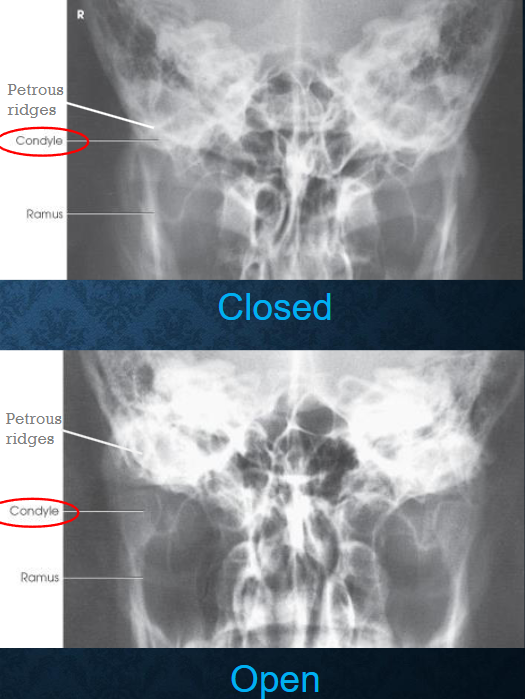

AP axial TMJs

patient position:

supine or upright

posterior skull in contact with Bucky/table

part position:

MSP of head perpendicular

flex neck to place OML perpendicular to IR

one exposure taken with mouth closed

one exposure taken with mouth open, if not contraindicated

respiration suspended

CR:

35 degrees caudad

midway between TMJs, 3 inches above nasion

collimation:

1 inch beyond the lateral sides, superiorly to the glabella, and inferiorly to the lips

AP axial TMJs image criteria

mandibular condyles and fossae of the temportal bones

no rotation of head

closed mouth: minimal superimposition of petrosa on the condyle

open mouth: condyle and TMJ below pars petrosa